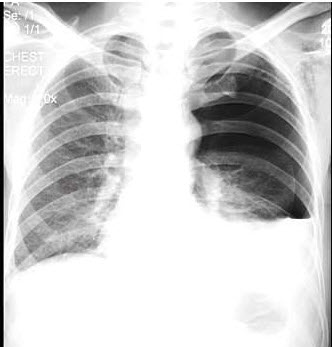

50、单项选择题

女,39岁,感胸痛、乏力,胸片如图,最可能的诊断是()